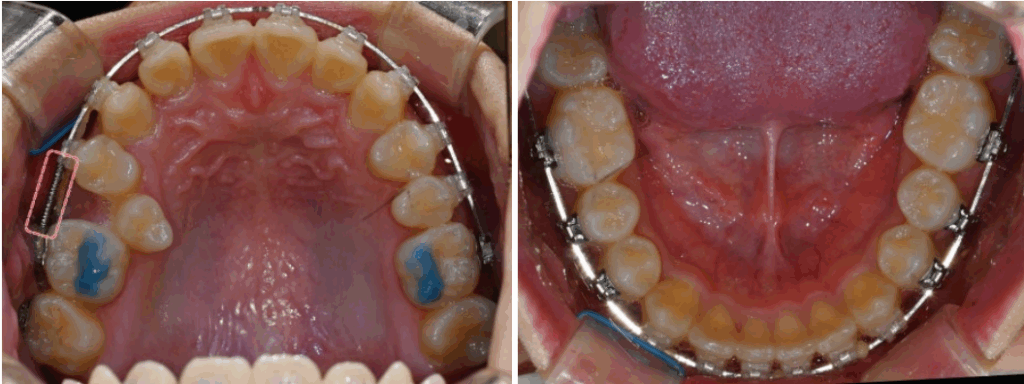

치아 배열을 하기 위해

1개의 위턱 미니 스크류와

오픈 코일 스프링을 활용한

비발치 교정을 계획하였으며,

배열 이후 기존 상태의 안모를

유지하는 방향으로 계획했습니다.

23.09.08

이소맹출된 오른쪽 위 작은 어금니 하나를

제외한 자연치 겉면에

클리피씨 브라켓을 부착했습니다.